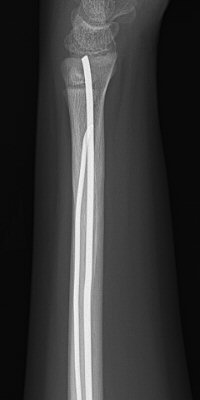

Monteggiafraktur: fraktur på ulna och samtidig luxation av caput radii. Man är inte helt överens om ulnafrakturen ska vara i den proximala tredjedelen [2] eller proximala två tredjedelarna av ulna [3]. Radiushuvudet kan också vara frakturerat istället för luxerat [2].

Monteggiafraktur, opererad med TEN-spik